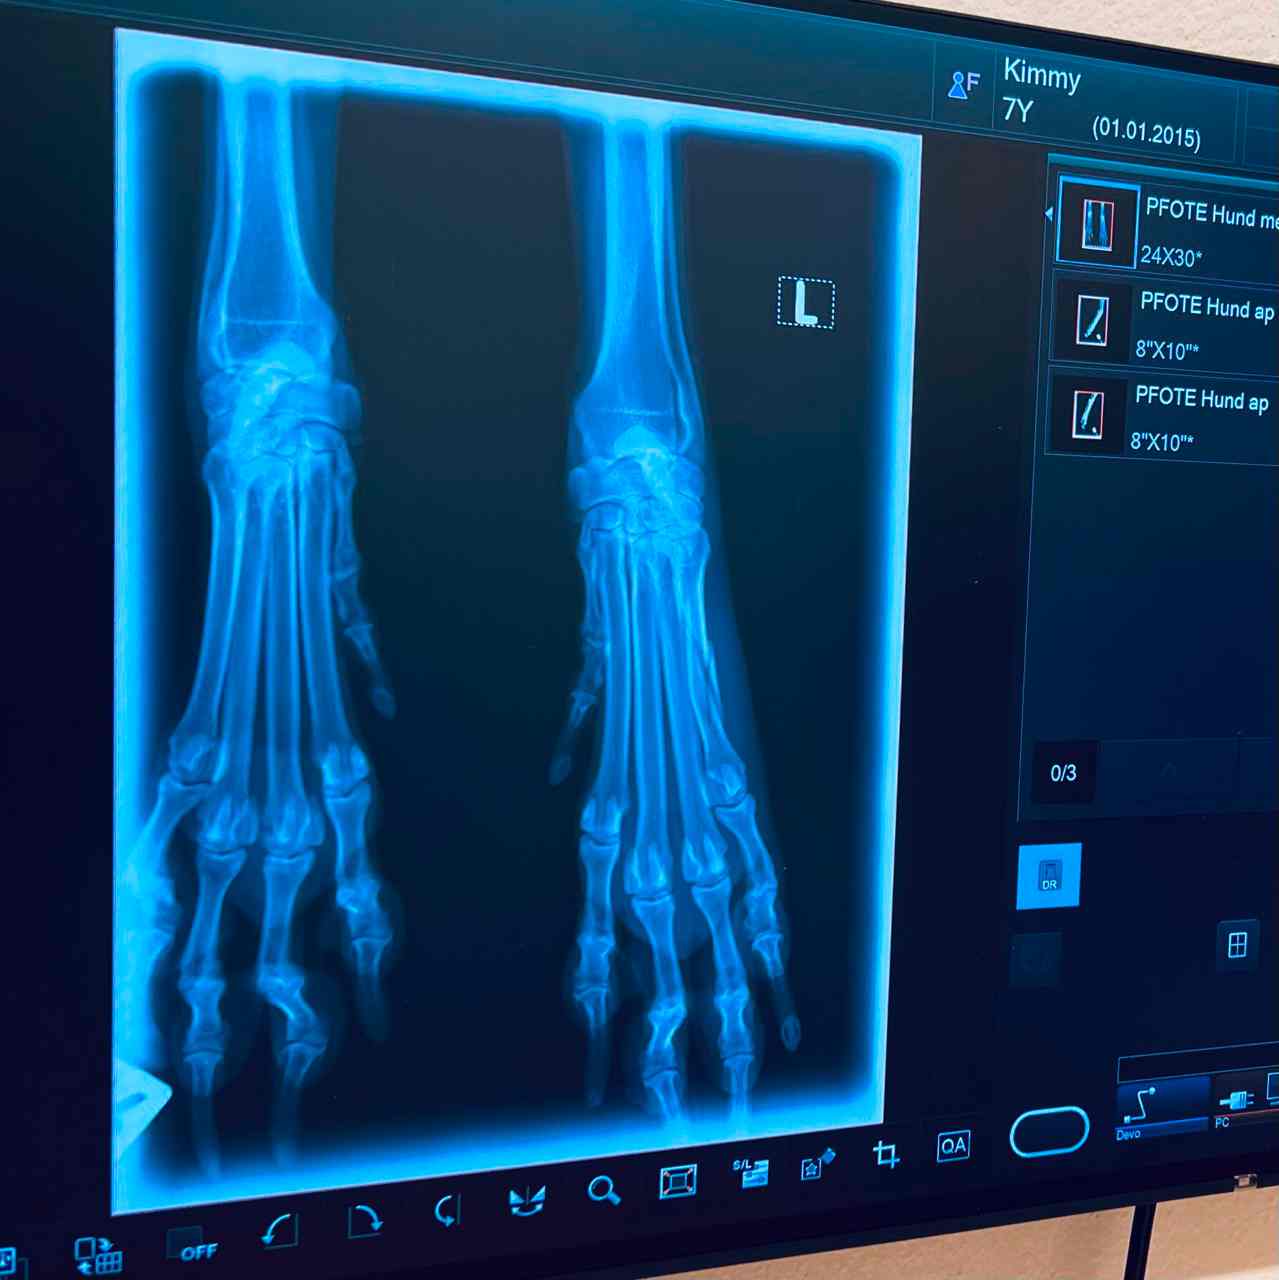

Wir bieten Röntgenuntersuchungen mit unserer digitalen Röntgenanlage. Dank der hohen Bildqualität des Röntgengerätes, lassen sich Verletzungen im Bereich des Skelett- und tw. des Bänderapparats schnell und einfach diagnostizieren. Auch Veränderungen an den Organen (Herz, Lunge oder z.B. Darm oder Blase) oder an den Zähnen können erkannt werden. Das Röntgenbild ist seit jeher ein wichtiges diagnostisches Hilfsmittel in der tierärztlichen Praxis. Die digitale Röntgentechnologie hebt dieses Hilfsmittel auf ein neues Niveau.

Wir haben 2022 in eine komplett neue Röntgenanlage am letzten Stand der Technik investiert. Das Hightech Gerät produziert erheblich bessere Bilder bei einer wesentlich verringerten Strahlendosis.

Der Flachbilddetektor von FUJIFILM ist das Herzstück unserer Röntgenanlage und macht den Unterschied in Hinblick auf die Bildqualität.

Die modernen Geräte ermöglichen uns hochauflösende Aufnahmen bei kleinstmöglicher Strahlendosis. Die intelligente Software von FUJIFILM stellt zum Schluss noch die Bildparameter perfekt ein.